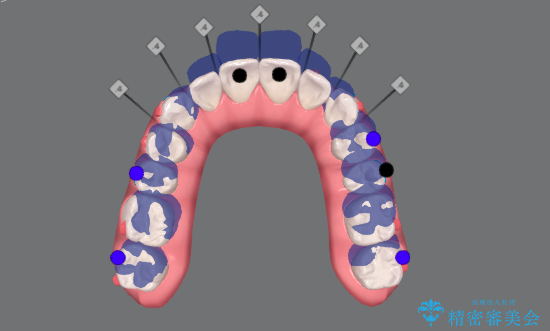

カリエール・マイクロインプラントを併用した歯の突出を改善する大きな遠心移動

- 口が閉じづらく、突出し歯が出っ歯に見えてしまうことの改善を求めて来院されました。

通常このような場合、抜歯してのワイヤー矯正治療も選択肢に入りますが、患者様の強い希望により抜歯を行わずマウスピースによる治療を選択しました。

カリエール・マイクロインプラントを用い、時間はかかりましたが大きく歯の後方移動が達成され、前歯の見た目が大きく改善されました。

大きな後方移動を達成するにはマイクロインプラントと日常的なゴムかけが大切です。